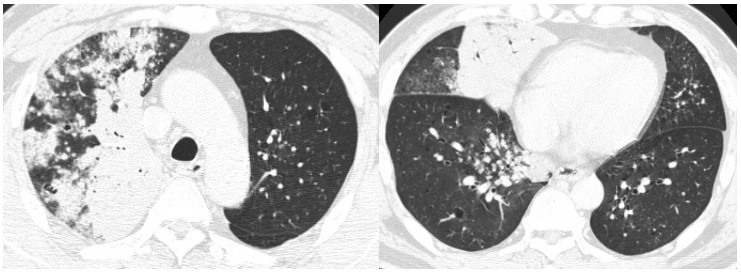

这个病人表现为两肺多灶、多斑片的实变,在右中下叶肺可以看到实变,仔细看两肺还有一些小点状。CT表现为右上叶明显实变,实变外周有小结节影,更低的层面可以看到右中叶明显实变影,另有磨玻璃影,右下叶有些实变影以及小叶中心的结节。在对侧,主要更多的是一些细小的点状。这个病人低烧,刚开始会想到炎症,但是这个病人不是常见的炎症表现,第一是因为边界比较清楚,第二是由于外周伴有小结节,所以这时就要小心,说明这个病变不是急性,要想到炎症之外的病变。这个病人最后诊断为肺腺癌。